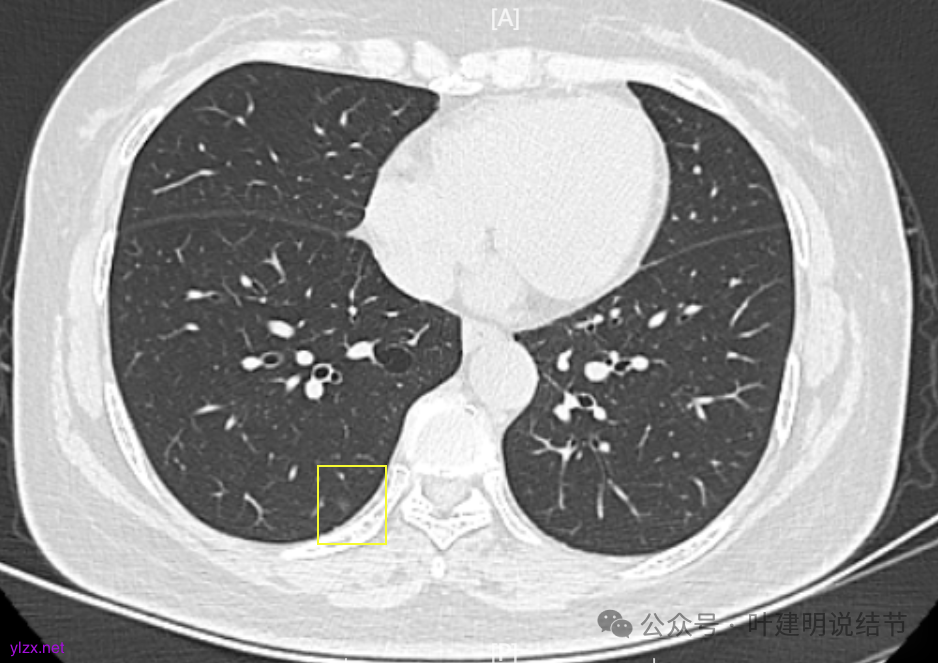

两肺多发磨玻璃结节,主病灶混合密度且有小血管进入,表面不平有毛刺,考虑微浸润性腺癌或浸润性腺癌可能性大,其余部分考虑原位癌或微浸润性腺癌,部分考虑肺泡上皮增生或不典型增生可能。总体上对比2022年说不上太明显的进展。但对于是否手术来讲,我仍倾向当年的意见,左侧的可以考虑近期亚肺叶(个人倾向楔切)切除,右侧的先随访,以后有进展并风险增加再考虑干预处理。因为要拉长两次手术的间隔,这样对机体的创伤与恢复更加有利一些。若定要仍不开刀,则建议要4-6个月复查,不过个人不太主张过于保守随访,对于像主病灶这种有少许实性成分的,不能保证肯定安全。意见供参考!

多发结节的处理到底该积极还是该保守,保守又该保守到怎样的程度?这真说不清楚。按既往经验,左上的混合密度结节应该是有一定风险的,既有毛刺,也有血管,还是偏实性成分,但它三年了,硬仍是几乎说不上明显进展。如果三年前按我的意见做了手术,是不是也是切早了呢?现在我仍建议她左侧的切了,是不是真的最合适的呢?其实我也不知道!因为我们对磨玻璃肺癌的认识仍很肤浅,对病因、发展以及如何处理仍在摸索之中。但从此例至少我们能得出的经验是:影像上考虑微浸润性腺癌且密度不太纯,或即使有微血管与毛刺征,仍不定会短期内进展。但是要说以此就得出结论以后类似影像表现的都不需要手术,仍可观察,或许也还是不一定正确的。我想医患双方仍得在不断的权衡与利弊分析当中选择自己想要的方案来随访或干预,基于当时的认知与知识面,基于当时的专家共识与指南,基于医生的临床经验与多学科讨论的结果。医生也要不断的总结反思与追求进步。